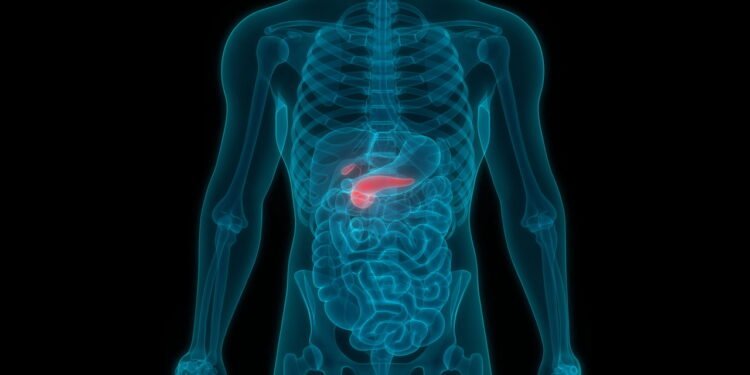

O pâncreas é um órgão essencial, localizado atrás do estômago, que desempenha duas funções vitais para a nossa saúde: a produção de enzimas digestivas e a regulação da glicemia (níveis de açúcar no sangue). Suas células produzem enzimas (como amilase, lipase e tripsina) que são liberadas no intestino delgado para quebrar carboidratos, gorduras e proteínas, facilitando a digestão e a absorção de nutrientes. Além disso, o pâncreas é o lar das ilhotas de Langerhans, que produzem hormônios cruciais como a insulina e o glucagon, responsáveis por manter o açúcar no sangue em equilíbrio.